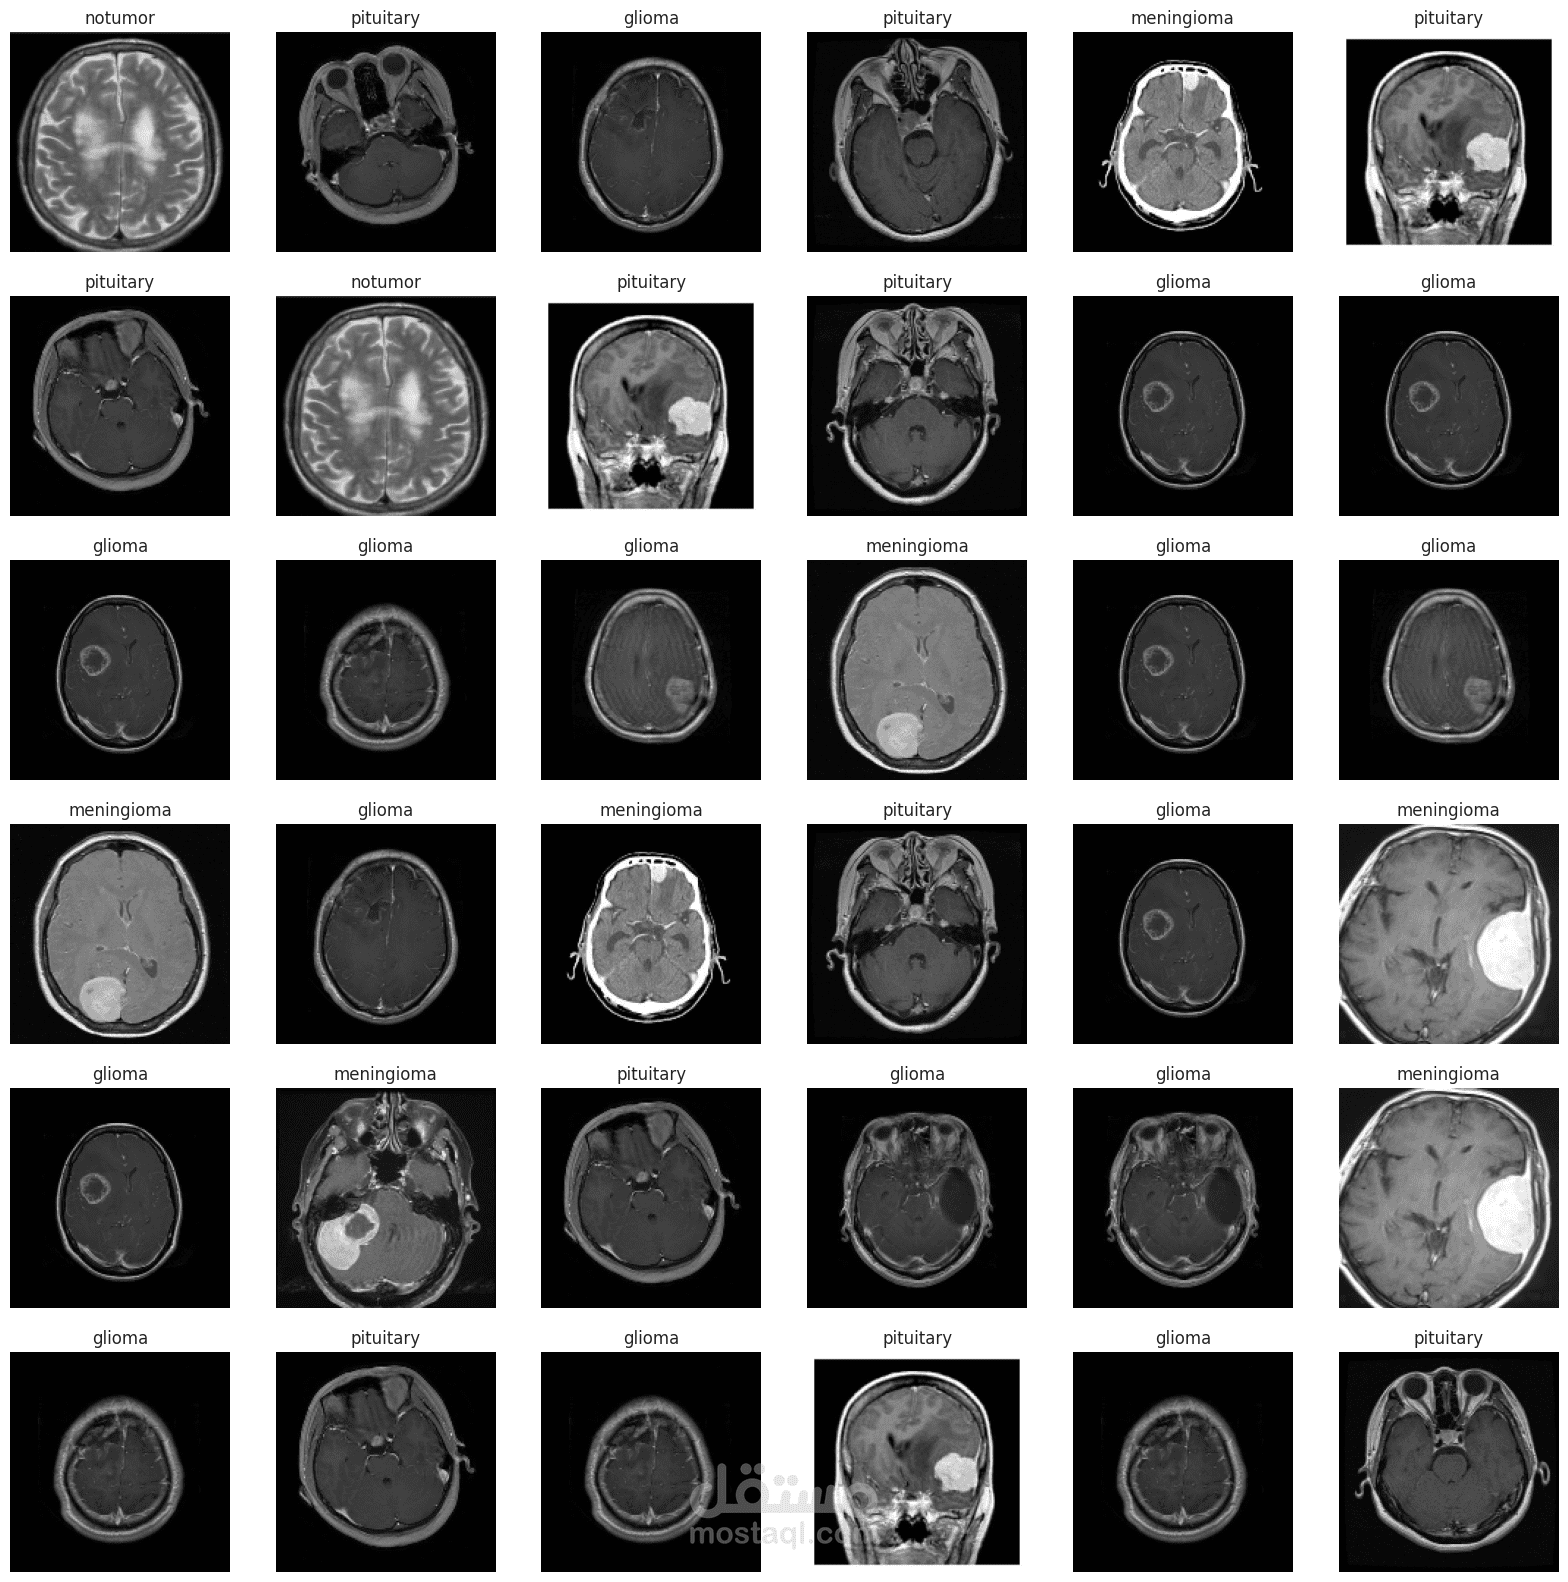

تصنيف نوع الورم (مثل الورم الأرومي الدبقي، الورم السحائي، الورم النخامي، أو عدم وجود ورم).

تحتوي هذه البيانات على 7022 صورة بالرنين المغناطيسي مصنفة إلى أربع فئات: الورم الأرومي الدبقي، الورم السحائي، الورم النخامي، وعدم وجود ورم. تم تحسين البيانات من خلال استبدال الصور غير المصنفة بشكل صحيح في مجموعة SARTAJ ببيانات أكثر دقة من figshare.